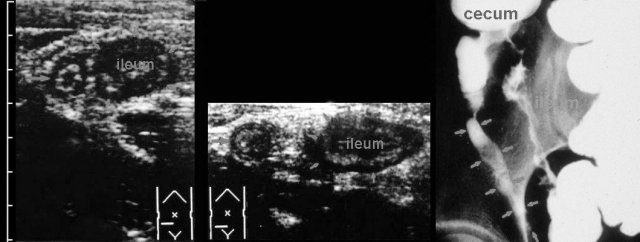

These images, though 30 years old, are still illustrative.

In this young man with suspected appendicitis both ileum and appendix (arrow) were thickened, due to ileocecal Crohn disease, also affecting the appendix.

Barium study confirms Crohn ileitis and shows irregular filling of the appendix, proving that this is a case of non-obstructive Crohn appendicitis.